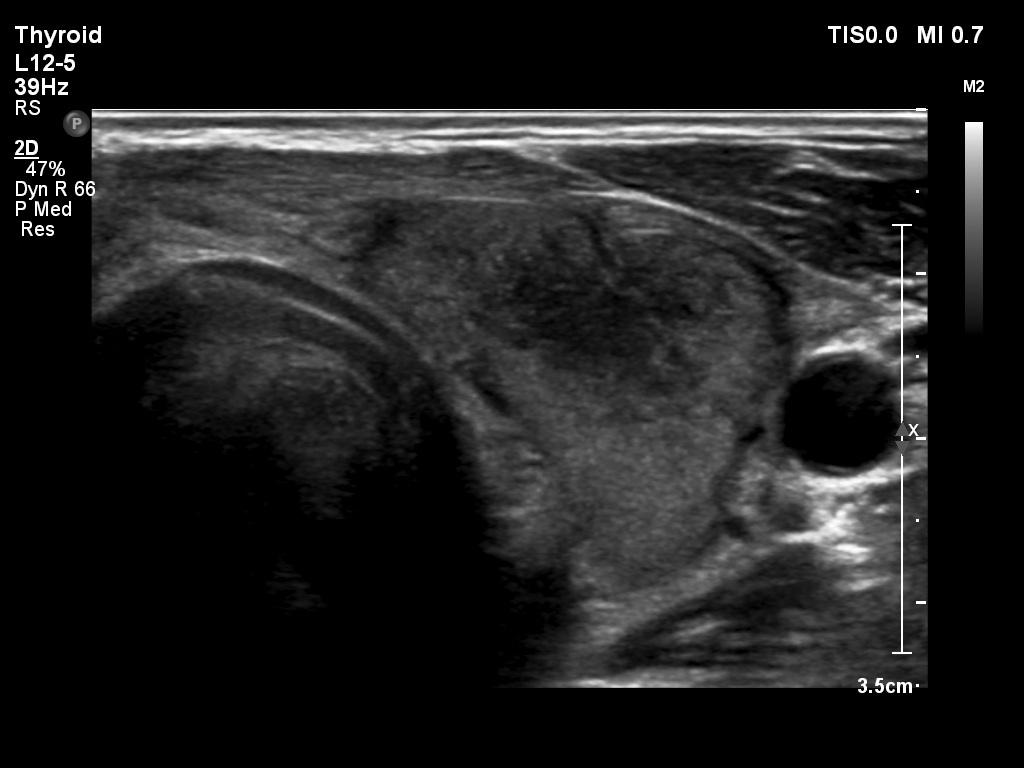

First examination (1st to 3rd rows of images):

Clinical presentation: A 47-year-old man was referred for evaluation of complaints suggesting subacute thyroiditis. He suffered from recurrent attacks of pain in the region of the thyroid radiating to the jaws. The pain was originally located to the left side of the neck but 2 weeks before the visit, both sides of the neck were affected. He had subfebrility, occasionally fever. He got 3 courses of antibiotics without any effect. The GP initiated investigation toward lymphoma of the neck.

Palpation: Both lobes were hard and painful.

Laboratory tests: euthyroidism with TSH-level 0.27 mIU/L, FT4 16.7 pM/L, CRP 35.1 mg/L, ESR 41 mm/H, aTPO 10 U/mL.

Ultrasonography: Both lobes presented hypoechogenic ill-defined areas. The echogenicity index was 80% in the right lobe while 20% in the left thyroid. The vascularization was significantly decreased.